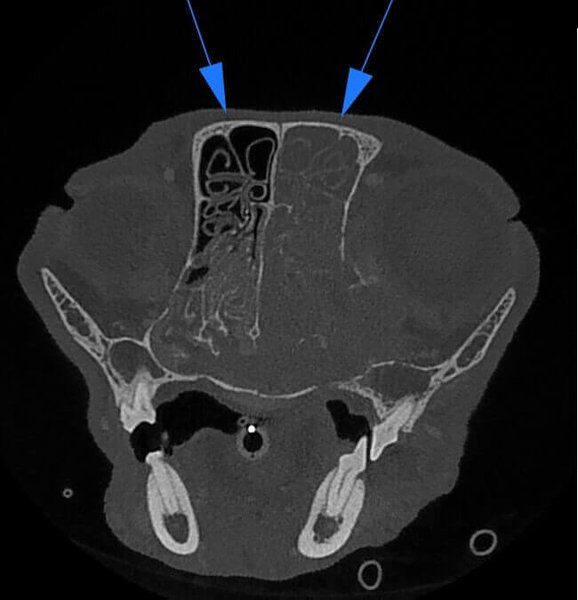

5G XL VET_Immagini Diagnostiche_Tumore nasale_1

5G XL VET_Immagini Diagnostiche_Tumore nasale_2

5G XL VET_Immagini Diagnostiche_Tumore nasale_3

5G XL VET_Immagini Diagnostiche_Tumore nasale_4

5G XL VET_Immagini Diagnostiche_Tumore nasale_5

5G XL VET_Immagini Diagnostiche_Tumore nasale_6

5G XL VET_Immagini Diagnostiche_Tumore nasale_7